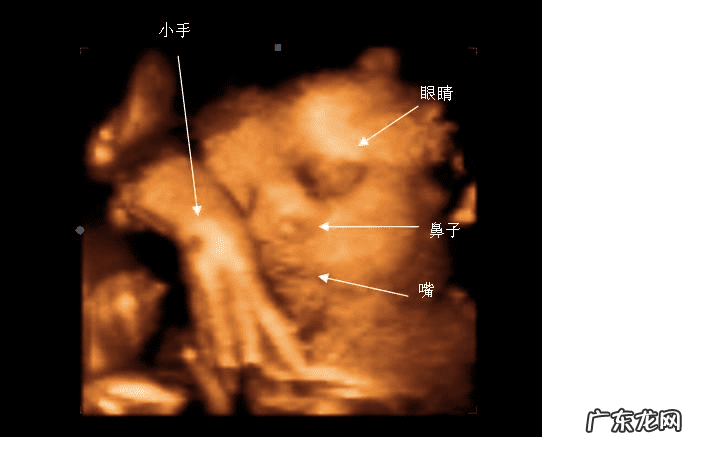

现在的彩超以四维彩超为主,三维彩超和四维彩超的区别主要在于在一个“时间维”,也就是说,三维彩超是图片,是静态的,四维彩超是录像,是动态的,可以让孕妈妈看到胎儿一连串的动作,所以四维看起来会更清楚明了,三维彩超只能是某个时间点上的照片,四维彩超的就可以做成DV那样连续的,可以刻录光盘 。三维彩超和高清四维彩超一样的有排畸的作用,高清四维彩超更加精确 。三维彩超侧重观察五脏六腑是否畸形,排除结构畸形 。四维彩超还观察运动神经系统是否正常,运动是否协调 。

三维彩超、四维彩超的图像则是后期生成的,并不是说观察到的图像就是三维、四维的,而是仍然用普通彩超观察,然后通过仪器中的转换软件将观察到的平面图像转成三维、四维的立体图像,说得更直白一点,如果将你的家用电脑中装上类似软件,你就可以把普通B超的图像自己在家里转换成立体的了 。

【三维彩超价格 三维彩超多少钱一次】在诊断的意义上,三维彩超、四维彩超没有任何对诊断更有利的地方,只不过是不懂得B超图像的人也能看出模样而已 。它们的意义也就在于,您能看见宝宝还在肚子里的模样了 。

四维彩超可立体显示胎儿的颜色、面、各器官的发育情况,甚至胎儿在母体里的状态也可以观察到;对胎儿畸形,如唇裂、腭裂、骨骼发育异常、心血管畸形等能早期诊断 。了解胎儿宫内动态的一个胎动过程,再者动态摄录胎儿宫内资态,可以让孕妈妈看到胎儿一连串的动作,所以四维看起来会更清楚明了,还可以留作永久的纪念 。三维彩超只能是某个时间点上的照片,四维彩超的就可以做成DV那样连续的,可以刻录光盘 。而且四维彩超不存在射线、光波和电磁波等方面的辐射,对人体的健康没有任何影响,现今医学上并没有对人体的健康有任何影响的报道 。